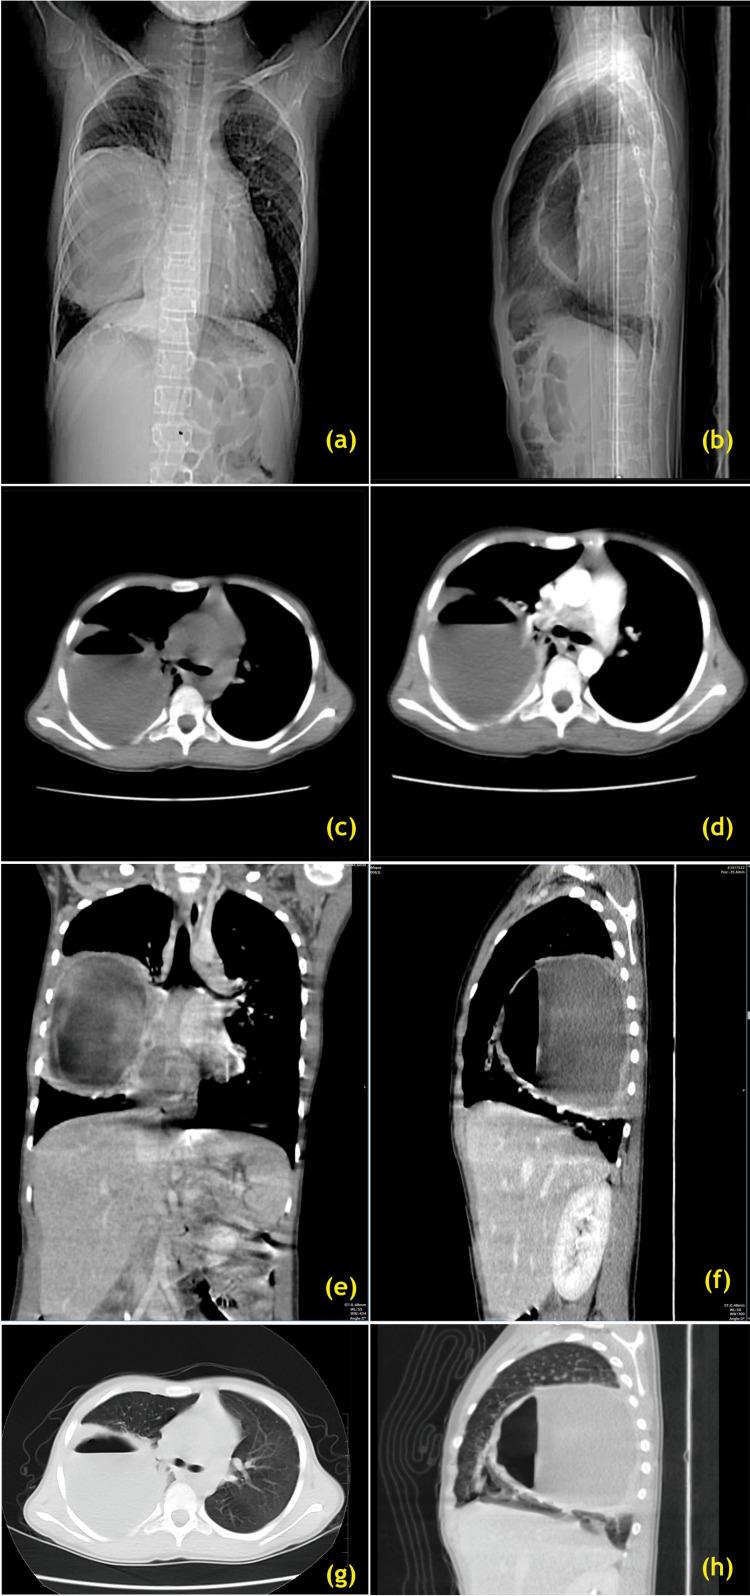

Pediatric lung abscess is a rare and poorly studied disease entity. In the past, prolonged courses of intravenous (IV) antibiotics have been successfully used; however, with the advent of interventional radiology, the main therapeutic approach is through percutaneous placement of pigtail catheters with ultrasound and computed tomography (CT) direction, where available. The pathogen yield identified from fluid samples of the abscess has dramatically increased owing to the greater invasive measures, such as aspiration and drainage, as well as enhanced microbiological diagnostic methods, which also include polymerase chain reaction testing. In our case report, in 2012 when the patient was two years old, she was diagnosed with pulmonary Koch's and underwent anti-Koch's therapy, category 2. High-resolution CT of the chest revealed a large lobulated cavitary lesion with an air-fluid level suggestive of a right lung abscess. After initial therapy with IV antibiotics for three weeks and a negative tuberculosis work-up, she underwent right limited lateral thoracotomy and drainage with decortication of the right lung abscess (LA) in 2019 via a left endobronchial tube with a bronchial blocker (general endobronchial anesthesia). All samples sent for histopathologic examination after surgery yielded negative results, and she was discharged after a course of injectable antibiotics for 21 days. She remained almost symptom-free for the next four years. Thereafter, she presented with a right LA recurrence due to a thick-walled cavitary lesion, with a severely damaged right lower lung lobe resulting in right lower lobectomy under single-lung ventilation (double-lumen endotracheal tube No. 26 Fr.). Culture results should guide management, particularly for immunocompromised patients, as the LA may be attributed to complications arising from underlying conditions. Primary lung abscesses (PLA) in children are typically caused by  and . Compared to adults, children with PLA and secondary lung abscesses have a meaningfully greater rate of recovery.

小儿肺脓肿是一种罕见且研究较少的疾病实体。过去,长期静脉使用抗生素已成功应用;然而,随着介入放射学的出现,主要治疗方法是在有条件的情况下,通过超声和计算机断层扫描(CT)引导经皮放置猪尾导管。由于采用了更具侵入性的措施,如抽吸和引流,以及改进的微生物诊断方法,包括聚合酶链反应检测,从脓肿液体样本中鉴定出的病原体数量大幅增加。在我们的病例报告中,2012年患者两岁时被诊断为肺结核并接受了2类抗结核治疗。胸部高分辨率CT显示一个大的分叶状空洞性病变,伴有气液平面,提示右肺脓肿。在静脉使用抗生素初始治疗三周且结核检查结果为阴性后,她于2019年通过带有支气管封堵器的左支气管内导管(全身支气管内麻醉)接受了右肺局限性外侧开胸手术及右肺脓肿剥脱引流术。术后送检的所有组织病理学检查样本结果均为阴性,在接受了21天的注射用抗生素治疗后她出院了。在接下来的四年里她几乎没有症状。此后,她因厚壁空洞性病变出现右肺脓肿复发,右肺下叶严重受损,导致在单肺通气(26F双腔气管内导管)下行右下肺叶切除术。培养结果应指导治疗管理,特别是对于免疫功能低下的患者,因为肺脓肿可能归因于潜在疾病引起的并发症。儿童原发性肺脓肿(PLA)通常由 和 引起。与成人相比,患有PLA和继发性肺脓肿的儿童恢复率明显更高。